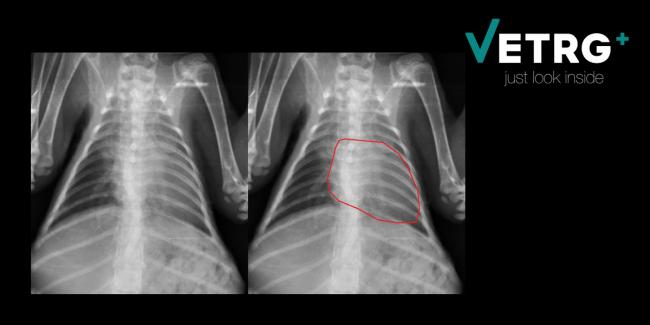

В области ателектатических мест при уступчивой грудной клетке рёберная стенка обыкновенно мало-помалу несколько западает, и вообще на детской грудной клетке, как более уступчивой, все клинические явления выражены обыкновенно яснее. В особенности при вдохе часто наблюдается втягивание нижне-боковых частей грудной клетки, как при стенозе гортани, так как и при ателектазе лёгкого, несмотря на усиленное напряжение дыхательных мышц, поступает недостаточно воздуха, например, вследствие закупорки бронха, или усиленное сокращение диафрагмы втягивает мягкие нижние части грудной клетки.

В зависимости от величины и локализации пораженного участка легкого развиваются клинические проявления. Довольно часто за клинической картиной основного заболевания не видно проявлений ателектаза. Кожные покровы у новорожденного могут быть бледны или синюшны; у ребенка — явная одышка. Врач, прослушивающий легкие с помощью фонендоскопа, не слышит дыхания в том месте, которое поражено, или слышит ослабленное дыхание. Перкуторный звук над участком ателектаза укорочен.

Помимо опроса и объективного осмотра, включающего перкуссию и аускультацию грудной клетки, проводят рентгенологическое исследование в двух положениях тела (в 2-х проекциях). Это основной метод обнаружения ателектазов легких.

На рентгеновских снимках выявляют следующие признаки, указывающие на спадение легочной ткани:

Однородное затемнение в области поражения. Размеры тени зависят от вида ателектаза: при долевом выявляется обширное затемнение, при сегментарном — в виде клина или треугольника, расположенного вершиной к корню легкого, дольковые ателектазы множественные и похожи на очаговую пневмонию. Дистензионный ателектаз расположен низко, около диафрагмы, имеет небольшие размеры и вид поперечных полос или темных дисков. Смещение органов: при компрессионном ателектазе смещение наблюдается в здоровую сторону, так как на стороне поражения давление больше, при обтурационном, наоборот – смещение будет в сторону ателектаза, так как на стороне поражения нарастает притягивающее отрицательное давление. Подъем купола диафрагмы – это видно по расположению печени.